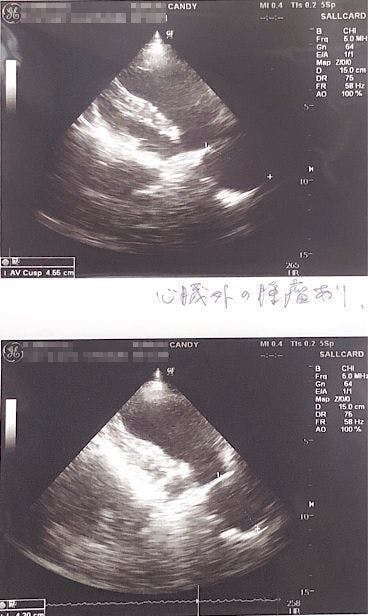

エコーを撮ったところ、体の中心に腫瘍の影があるのが見えると言われました。

バリウム飲んで検査してもらったところ、矢印の部分に腫瘍があり(白い部分は食道)、それが食道を押し上げているため、飲んだ水を吐いたりするとのことでした。(この時点で5センチほどの大きさの腫瘍でした。)

↑腫瘍の場所が体の奥のにある為、CT検査できる大学病院で検査してから手術するかどうか決めたほうがいいと言われました。

「腫瘍が心臓を圧迫していて左の肺を押しつぶしている為(右肺のみの呼吸)、通常の半分の呼吸しか出来ていず、少し歩くだけでもすぐに苦しくなる状態です。」